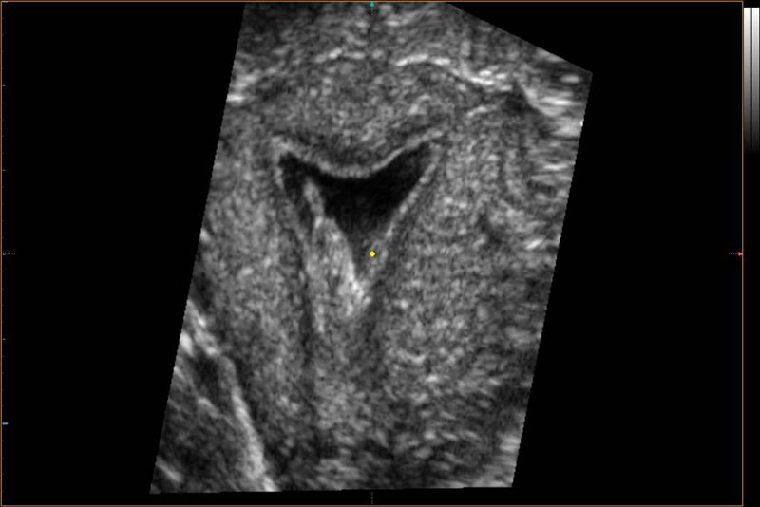

Синехии обладают отличной от других тканей матки плотностью, потому они легко визуализируются в ходе ультразвукового исследования. В ходе УЗИ можно определить как собственно место их расположения, так и степень закрытости ими органа, то насколько он деформирован и т. д.

Если необходимо в диагностических целях забрать ткани синехий на гистологию, то делается это в ходе гистероскопии. Этот же метод может применяться и для осмотра полости матки в диагностических целях (если нет препятствий для проникновения оборудования в ее полость).